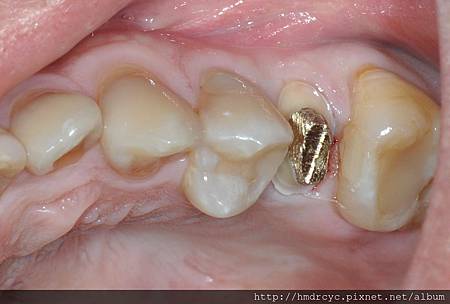

打上鑄心後 仍然可以恢復牙齒高度寬度

根管治療完成先裝鑄心恢復

裝上鑄心

裝上鑄心後牙齒的高度寬度都恢復

假牙也可以穩定的包覆在牙齒上